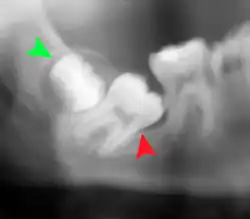

Las muelas del juicio impactadas se clasifican según la dirección y la profundidad de la impactación, la cantidad de espacio disponible para la erupción dental y la cantidad de tejido blando o hueso (o ambos) que las recubre. La estructura de clasificación ayuda a los clínicos a estimar los riesgos de impactación, infecciones y complicaciones asociadas a la extracción de las muelas del juicio.[6] Las muelas del juicio también se clasifican por la presencia (o ausencia) de síntomas y enfermedad.[7]

Las muelas del juicio impactadas suelen describirse por la dirección de su impactación (la inclinación hacia delante o mesioangular es la más común), la profundidad de la impactación y la edad del paciente, así como otros factores como la infección preexistente o la presencia de patología (quistes, tumores u otras enfermedades):[5] Cada uno de estos factores se utiliza para predecir la dificultad (y la tasa de complicaciones) al extraer un diente impactado, siendo la edad el factor predictivo más fiable,[8] que la orientación de la impactación.[9]

Otro sistema de clasificación que se suele enseñar en las facultades de Odontología de Estados Unidos es el conocido como Clasificación de Pell y Gregory. Este sistema incluye un componente horizontal y otro vertical para clasificar la ubicación de los terceros molares (aplicable predominantemente a los terceros molares inferiores): la relación del tercer molar con el nivel de los dientes que ya están en la boca, siendo el componente vertical o x, y con el borde anterior de la rama, siendo el componente horizontal o y.[10]